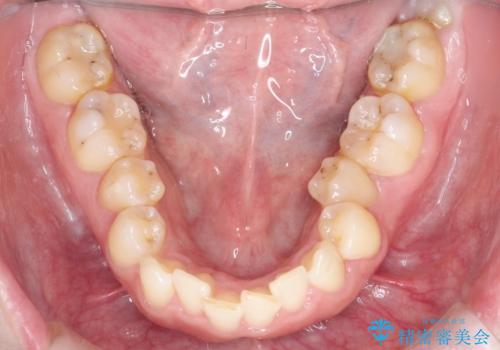

【インビザライン】前歯の凸凹を治したい。

- 前歯の凸凹を主訴に来院されました。

深い噛み合わせも同時に治療を行う計画を立て、インビザラインを使用して歯並びの改善を行うことができました。

叢生改善のために遠心移動とIPRを行なっています。